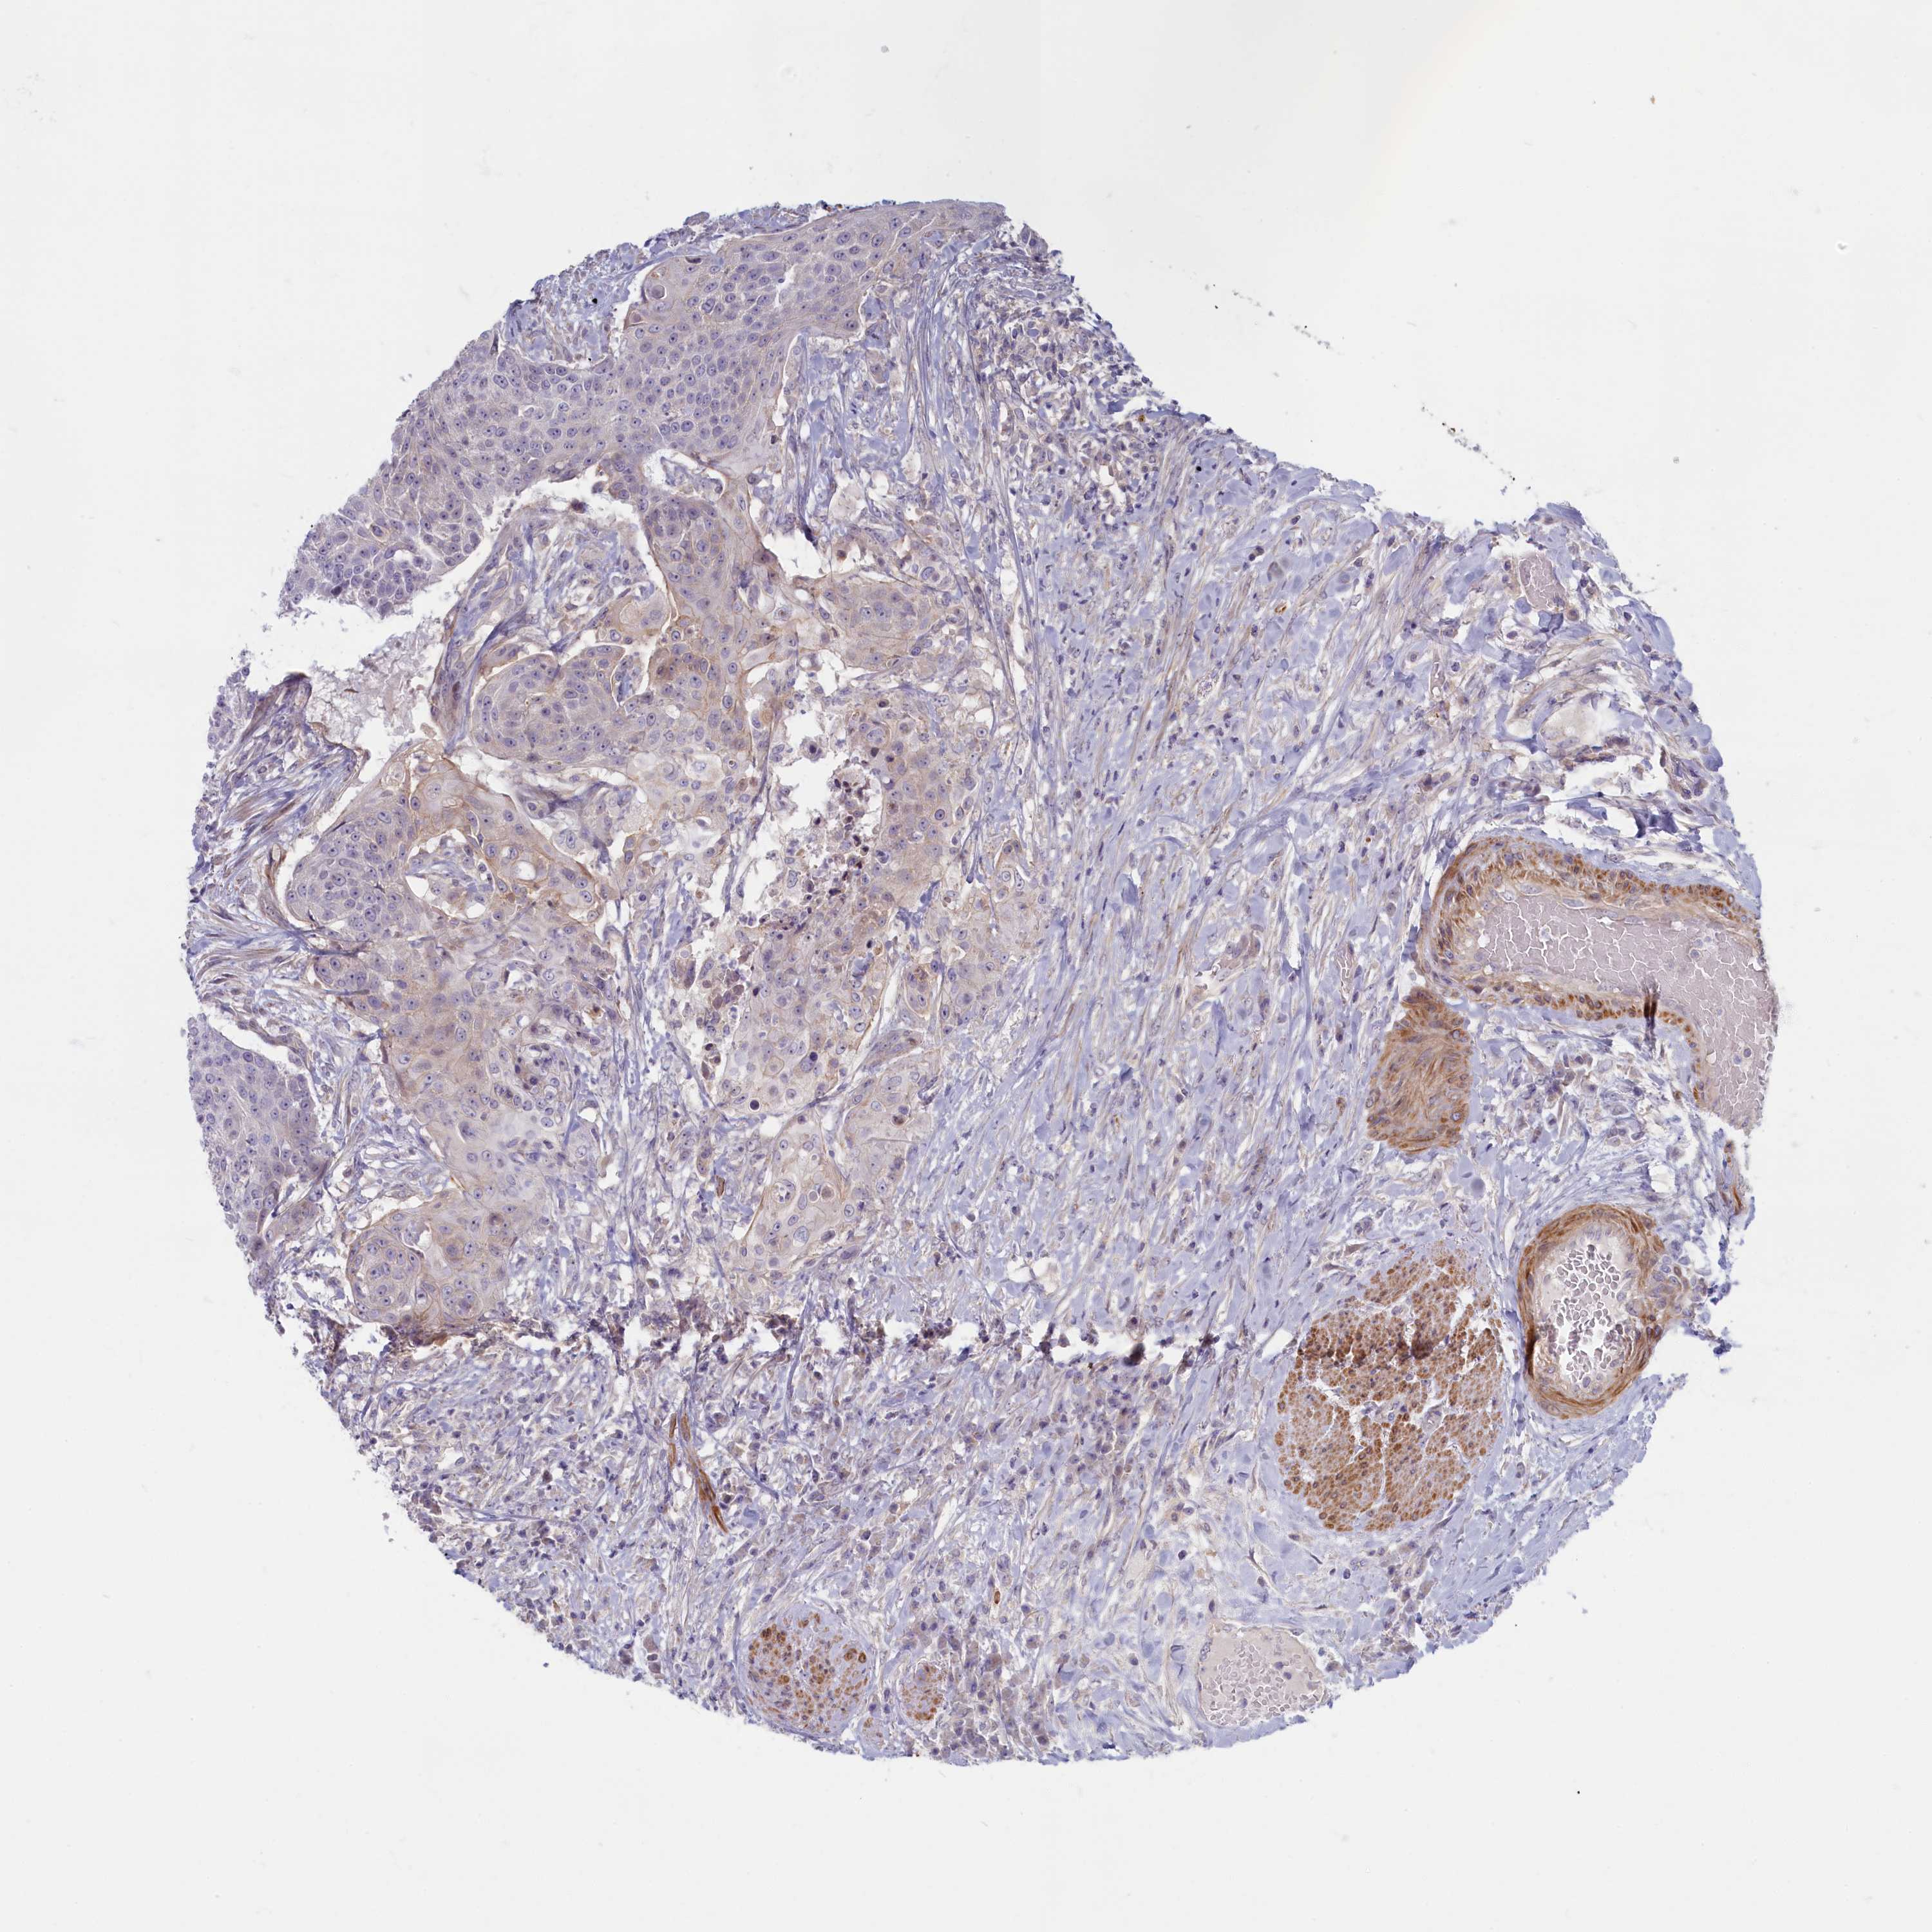

UROTHELIAL CANCER - Protein expressioni

A mouse-over function shows sample information and annotation data. Click on an image to view it in a full screen mode. Samples can be filtered based on level of antibody staining by selecting one or several of the following categories: high, medium, low and not detected. The assay and annotation is described here.

Note that samples used for immunohistochemistry by the Human Protein Atlas do not correspond to samples in the TCGA dataset.

Antibody stainingi

Antibody staining in the annotated cell types in the current human tissue is reported as not detected, low, medium, or high, based on conventional immunohistochemistry profiling in selected tissues. This score is based on the combination of the staining intensity and fraction of stained cells.

Each image is clickable and will lead to virtual microscopy that enables deeper exploration of all samples and also displays staining intensity scores, fraction scores and subcellular localization as well as patient and tissue information for each sample.

Antibody HPA041169

Staining

High

Medium

Low

Not detected

Intensity

Strong

Moderate

Weak

Negative

Quantity

>75%

75%-25%

<25%

None

Location

Nuclear

Cytoplasmic/membranous

Cytoplasmic/membranous,nuclear

Urothelial carcinoma, High grade

Urothelial carcinoma, Low grade